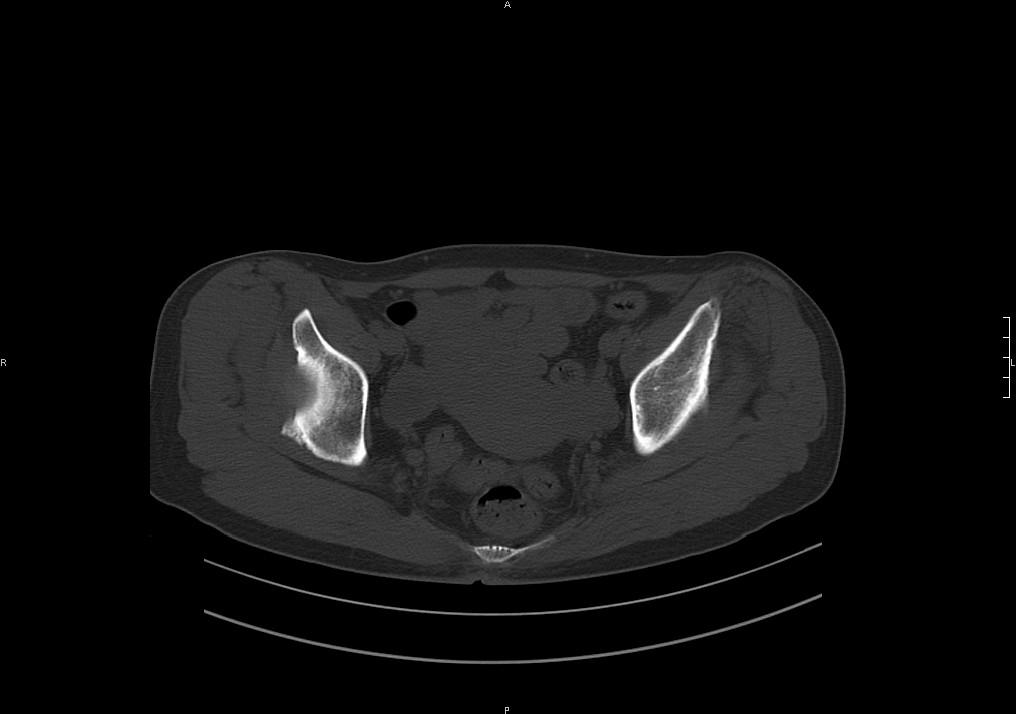

标题: CT19780左髋关节疼痛伴跛行1年,加重1个月。无菌性坏死? [打印本页]

标题: CT19780左髋关节疼痛伴跛行1年,加重1个月。无菌性坏死?

没报年龄,但髋臼有骨质增生, 考虑退行性变,坏死不明显。

滑膜增厚钙化,关节鼠及滑囊积液,髋臼增生。考虑骨性关节病

髋臼平浅,股骨头覆盖率减小,考虑双侧髋关节发育不良伴退行性变。

考虑左髋关节退行性骨关节病;建议必要时行mri检查排除左侧股骨头缺血性坏死。